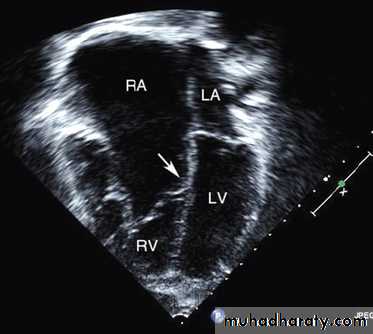

Ebstein anomaly consists of downward displacement of an abnormal tricuspid valve into the right ventricle.

The right ventricle is divided into 2 parts by the abnormal tricuspid valve: the 1st, a thin-walled “atrialized” portion, is continuous with the cavity of the right atrium; the 2nd, often smaller portion consists of normal ventricular myocardium.

RV output is decreased due to a combination of the poorly

functioning small right ventricle and tricuspid valve regurgitation,